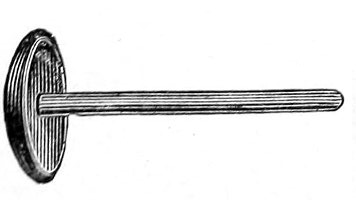

The uterine sound is an instrument by which the length of the uterine cavity may be determined (Fig. 15). The sound, which is a large surgical probe, somewhat curved to adapt itself to the normal shape of the uterine axis, is made of pliable metal, so that the curvature may be changed readily to suit any case. The sound is graduated, and at a position of 2½ inches from the tip is a small elevation marking the length of the normal uterine cavity.

Fig. 15.—Uterine sound.

The uterine sound was at one time used a great deal to determine the length and direction of the uterus, and 35 perhaps to assist in determining the character of the uterine contents or of the endometrium. With our present methods of examination, however, the sound is of but little if any use. The size and direction of the uterus can in nearly all cases be determined by bimanual examination. The use of the uterine sound is by no means free from danger. Many cases of septic endometritis and salpingitis have been caused by it, and the physician has often unintentionally committed an abortion by passing the sound in a pregnant woman. The uterine sound should never be used in a routine way. It should never be used unless one expects to determine with it something that cannot be determined by simpler methods of examination.

The most thorough aseptic precautions should be observed when the sound is introduced. The vulva, vagina, and cervix should be cleaned and the sound should be sterilized. The sound should never be introduced if there is any suspicion of pregnancy.